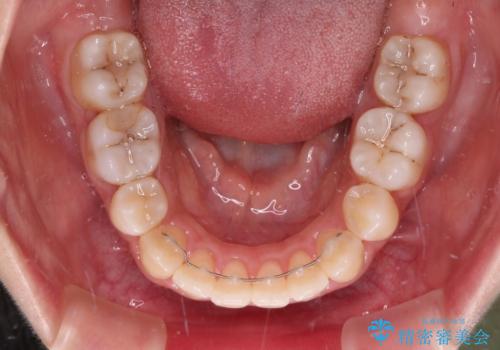

突出した口元が気になる ハーフリンガル装置による抜歯矯正

- 口元の突出感を気にして来院された患者様です。

通常では上下左右の第一小臼歯4本を抜歯しますが、下顎が左側にシフトしていたため、下顎左側のみ第二小臼歯を抜歯し、正中を合わせながら口元を下げる治療計画としました。

ハーフリンガルは、通常では表側のワイヤー矯正よりも治療期間がかかります。特に今回のように下顎左側をイレギュラーの第二小臼歯抜歯としたため、さらに時間がかかることが予想されました。

実際に治療をおこなってみると、2年を切る短期間で治療を終えることができました。